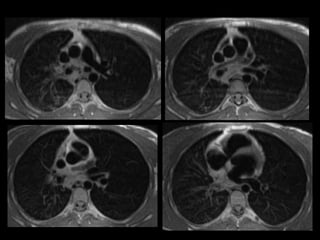

Mujer de 18 años con episodio de hemoptisis con

exploración ORL normal

• Otro caso

Varón de 56 años que consulta por hemoptisis